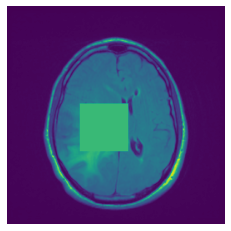

In figure 3, we present qualitative examples of different masking strategies. It is observed that, unlike context prediction and restoration, our method tends to propose targeted masks like the tumor regions or regions with abnormalities and avoids masking less helpful regions. However, it should be noted that Intelligent-Masking does not necessarily mask the tumor regions but considers all areas of interest that results in better feature learning. Examples of other masking samples are provided in supplementary materials. Furthermore, in medical images, unlike natural scenes, the structures are very local with imbalanced information throughout an image. Therefore, random masking strategies as shown in Fig 3 operate ineffectively by masking non-informative regions.

Figure 2: Qualitative examples of compared method’s strategies for masking

Figure 3: More qualitative examples of different distorting strategies including our method. We show the different self-supervised mechanisms on both datasets of MR (rows: 1-3) and ultrasound (rows: 4-6) images for lower-grade glioma and breast cancer diagnosis respectively. We include both images of normal (rows: 1,4) and cancer (rows: 2,3,5,6) conditions for each dataset. We also observe that our method treats each image based on its context information with no predetermined strategy.